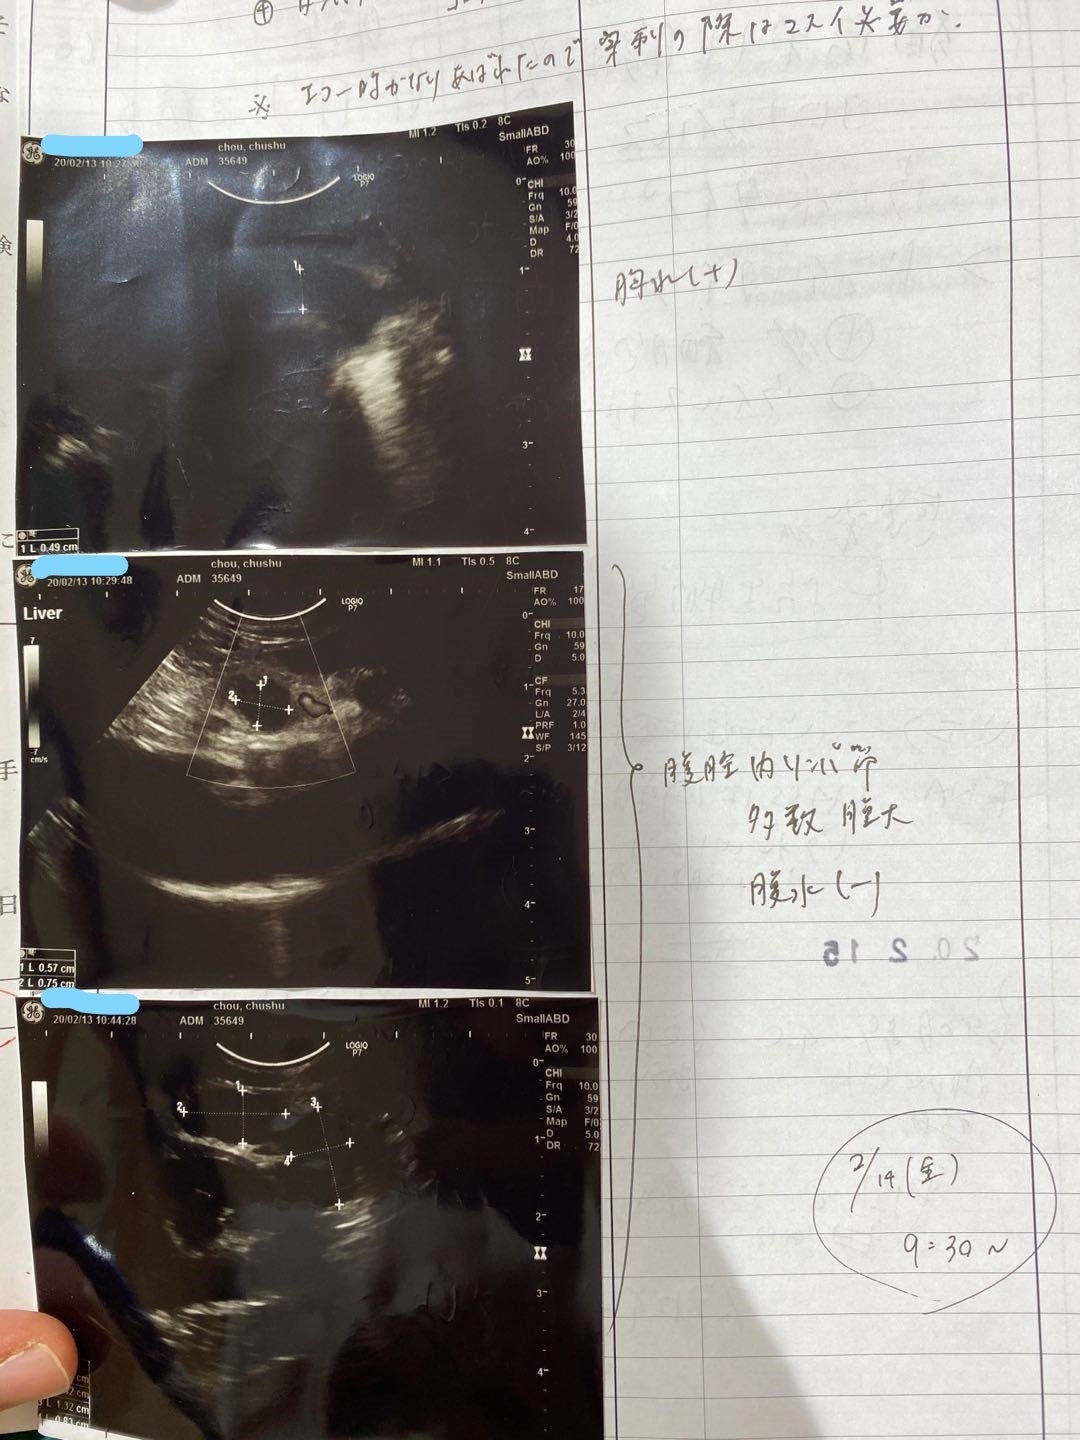

2/13去勢手術するため、身体検査をするとき、肺の中に薄い水影があって、念のため詳しい検査を行いました。

症状が軽い、判断が難しく、少し観察の時間が必要けど、最悪の場合はFIPを罹っているの可能性があると言われて、でも別の病気の可能性もあると言われました。3/9でレントゲン検査すると、水影が少し薄くになって、4月の検査も同じになって、FIPの可能性ではないかもと思います。けど、5月の検査はあまり変わらないになって、22日で急に発症になりました。前を振り返って見て、ずっと自分を責め続いている。

腹水がたまっています

肉芽腫が見つかります